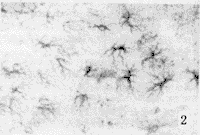

在各组仔鼠经TH免疫细胞化学反应染色后的中脑黑质、腹侧被盖区和AC平面的尾状核切片中,均可见到反应物呈灰黑色颗粒状的TH反应阳性神经细胞和神经纤维及其终末。但高锰组仔鼠黑质网状部、腹侧被盖区和尾状核的TH反应强度明显比对照组和低锰组减弱,反应阳性产物的分布亦显著稀疏(图2)。经图象分析系统微机检测,上述各区TH反应阳性产物的平均相对密度明显减少,结果见表4。与上述光镜下的形态学观察相一致。

图2 黑质网状部 TH免疫反应染色切片 ×360